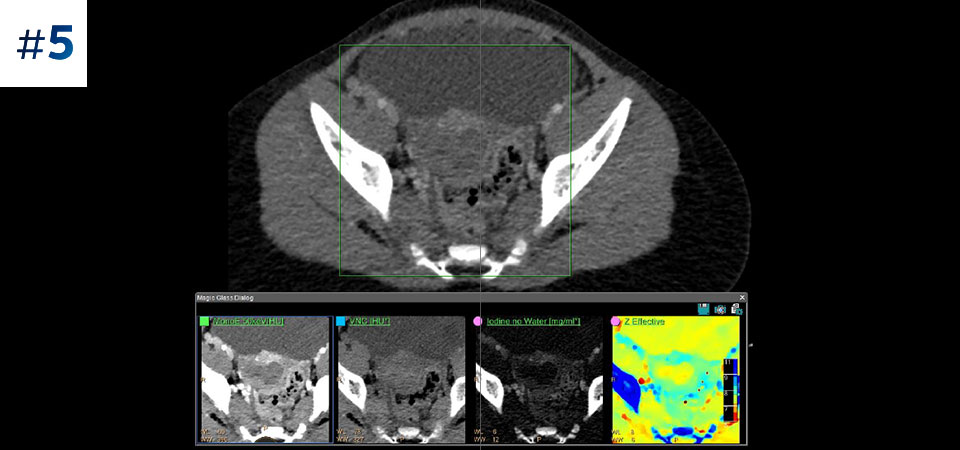

Брюшная полость/таз